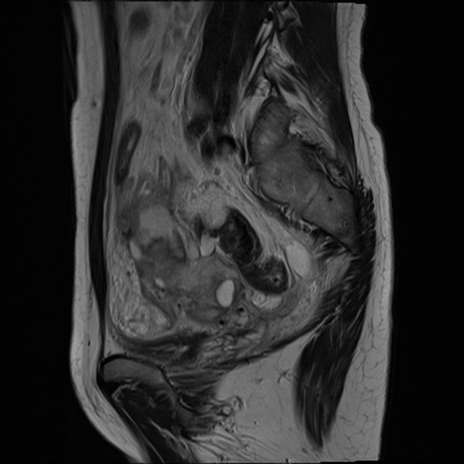

症例39 T2WI(矢状断像)

MRI(4日後)